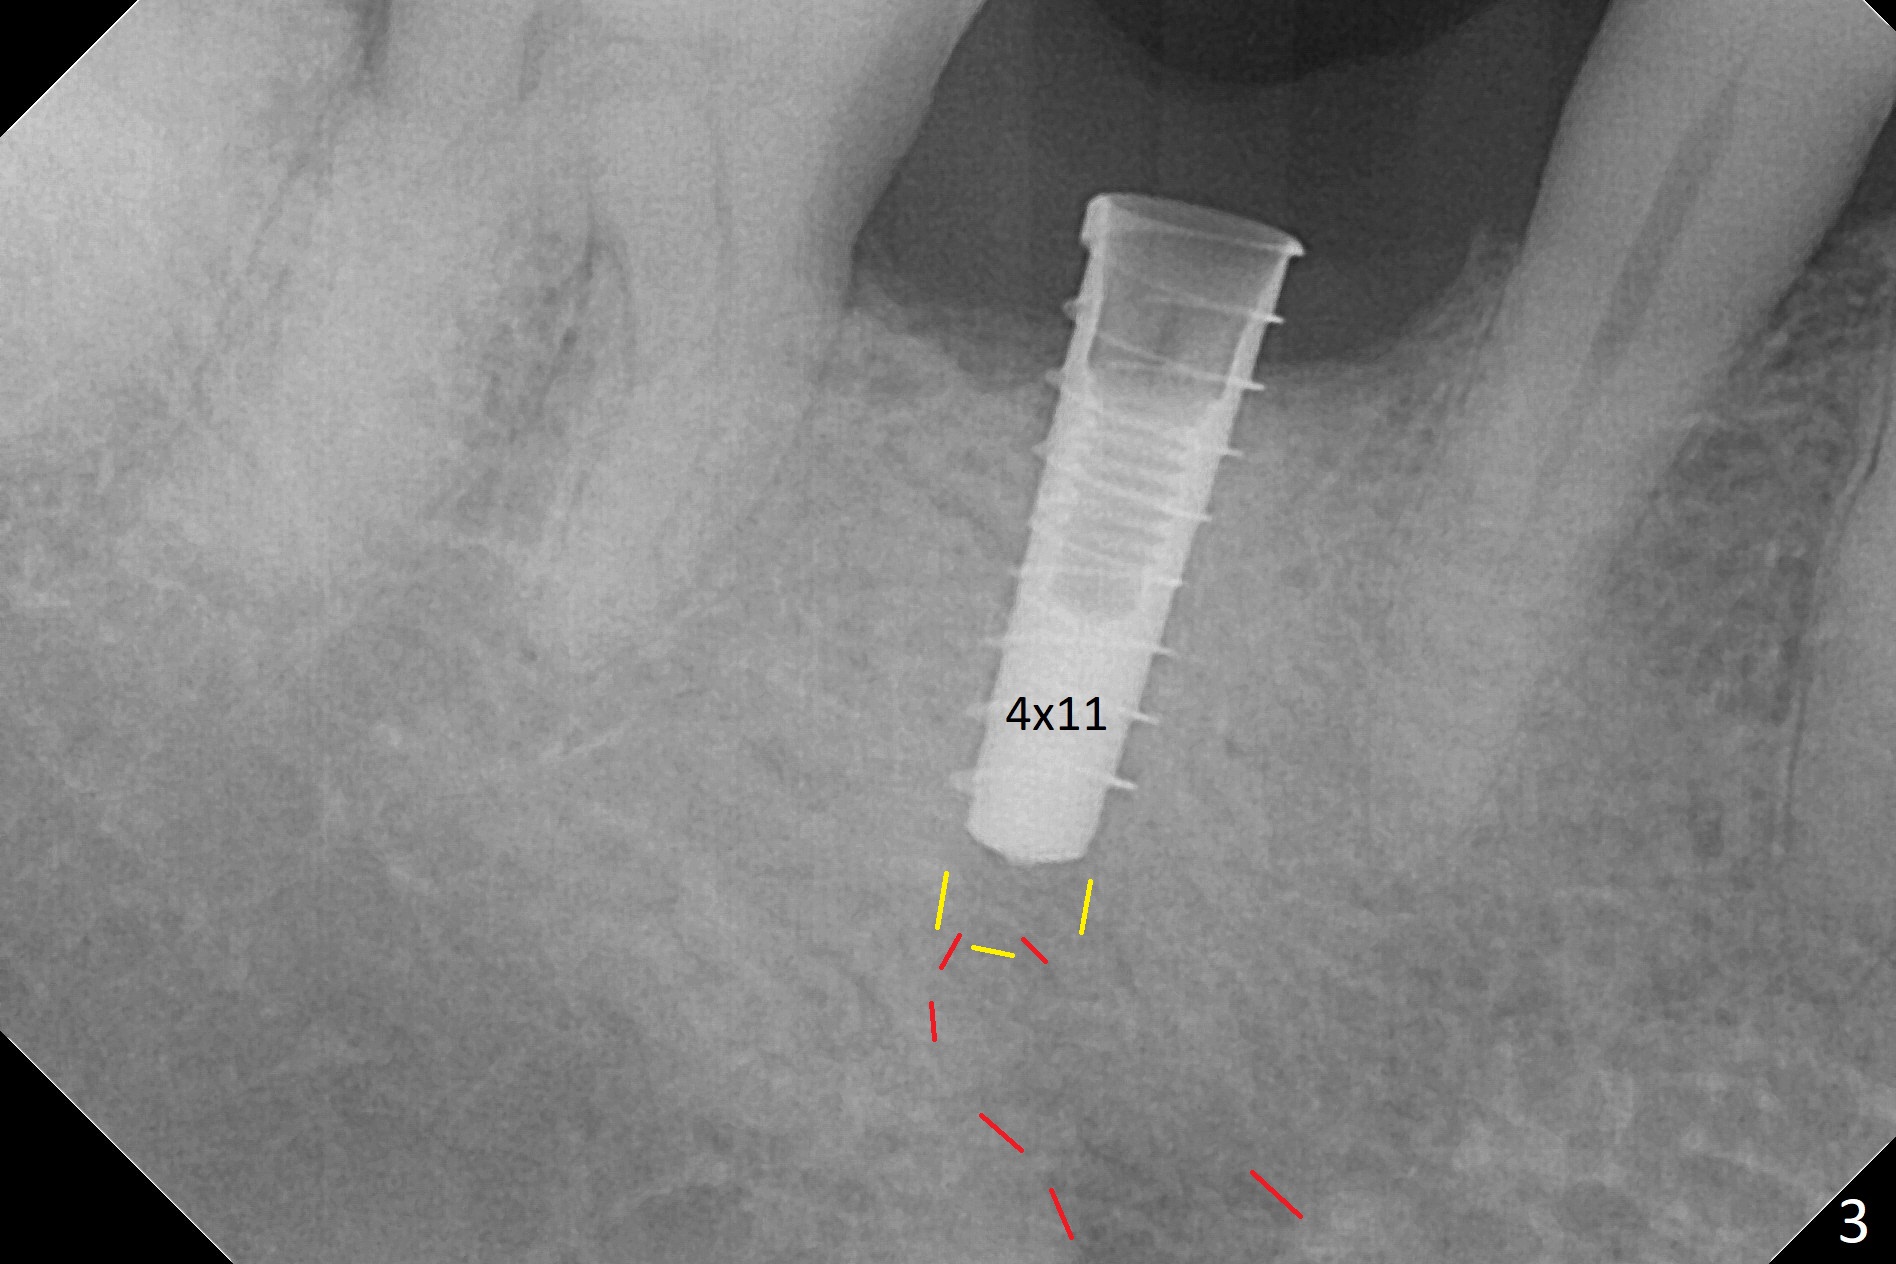

The retained deciduous tooth (lower right 2nd molar, Fig.1 T) has buccal apical infection and recession. After extraction, the initial depth of osteotomy is 11 mm over the flat socket bottom (Fig.2) without visible Mental Loop. Following 3.8 mm Magic Drill for 11 mm, a 4x11 mm dummy implant is placed partially due to hard bone; it appears that the apical osteotomy (Fig.3 yellow outline) overlaps the Mental Loop (red dashed line). For safety, a 4x9 mm IBS implant is placed with insertion torque 40 Ncm; a 5x5.7(4) mm abutment is immediately placed for an immediate provisional to cover the large socket and keep Vera graft in place (Fig.4 *). There is no postop paresthesia, probably due to the fact that the osteotomy is lingual to the Mental Loop. The provisional remains in place 7 days postop; its margin (Fig.5 arrow) covers the socket. The margin of the provisional is trimmed 1 month postop. Impression is taken nearly 3 months postop (Fig.6). The buccal plate looks atrophic 3 months postop (Fig.7 (immediately before cementation)), although there is no sign of periimplantitis. In the future, insert the immediate provisional inside of the buccal gingiva to make the buccal gingiva look bulky instead of buccal to it (Fig.5). The second drawback of placing an implant at the deciduous tooth area is that the crown is wide mesiodistally if orthodontic treatment is not rendered. Although there is lower anterior crowding, the patient declines orthodontic treatment. The bone density around the implant increases 7 months post cementation (Fig.8 *). The higher density bone seems to extend coronally 1 year 7 months post cementation (Fig.9). The dense bone apparently extends toward the abutment as well 3 years 5 months post cementation (Fig.10 curved arrows).